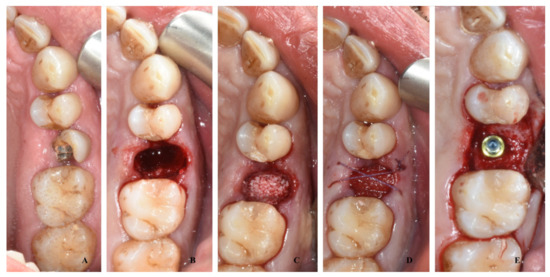

A total of ten patients (group B) after tooth extraction received bone harvesting from the mandibular ramus on the side of the extraction: under local anesthesia with 1:100,000 articaine, a small flap was elevated with a bur mounted on a handpiece (Autobone collector, Osstem, Micerium, Avegno, Italy), and an autologous particulated cortical bone graft was harvested (Figure 2). This bone graft was then placed inside the alveolar socket covered with a resorbable collagen matrix diameter of 8 mm sutured at the soft tissue with resorbable stitches (Figure 3).

Figure 3. A case of socket preservation performed with autologous bone harvested from the mandible placed inside the alveolar socket covered with a resorbable collagen matrix and the insertion of the dental implant after four months: preoperative image with decayed root (A); image after root extraction (B); image of socket filled with autologous bone graft (C); suture and collagen matrix (D); image at the time of implant surgery, with detail of cap screw (E).